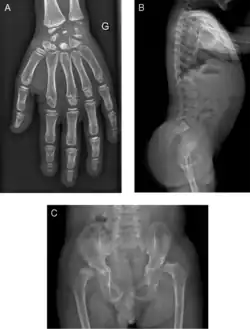

Radiograph of a WRS child presenting with dysplastic bone growth in various regions of the body. |

Initially, patients with neonatal or early-childhood onset diabetes are possible candidates for having Wolcott–Rallison syndrome.[1] The other features include multiple epiphyseal dysplasia, osteopenia, intellectual disability, and hepatic and renal dysfunction.[1] Patients having features that suggest Wolcott–Rallison syndrome can be referred for genetics testing. The key way to test for this disease is through genetic testing for EIKF2AK3 mutations.[7] Molecular genetic analysis can be done for the patient and the parents to test for inherited or de novo mutations. It can also show whether the patient's parents are heterozygotes or homozygotes for the normal genotype.[4] X-rays can show bone age in relation to actual age. In typical WRS patients the bone age is a few years less than the chronological age.[4][5][8][9] Hypothyroidism is rare in WRS patients but can occur.[4]